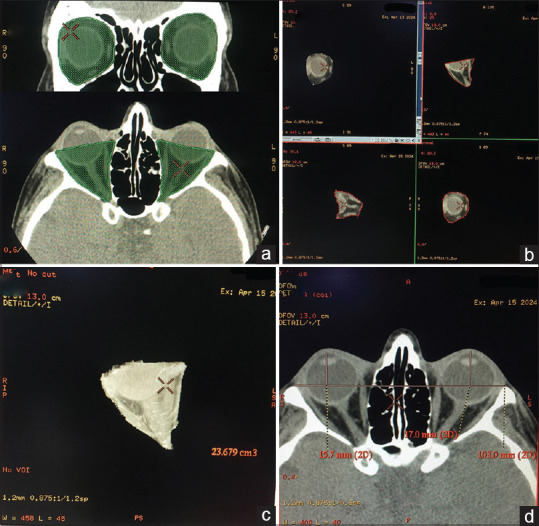

Purpose: To analyze the correlation between orbital computed tomography (CT) scan measurements including the fracture area (FA), the fracture location, the soft-tissue herniation volume (HV), the fractured orbital volume ratio (OVR) to the normal orbit, and the clinical enophthalmos in acute isolated orbital floor fractures.

Methods: We enrolled 100 patients with acute isolated unilateral orbital floor fractures from May 2017 to January 2021. Based on the CT scan findings, we measured the FA, HV, OVR, and fracture site. We assessed enophthalmos using both clinical (CE) and radiographic (RE) measurements. Additionally, we investigated the correlation between CE and the measured parameters, along with the relationship between the pattern of diplopia and the fracture site.

Results: We identified enophthalmos in 81% and diplopia in 78% of the patients with an acute blowout orbital floor fracture. CE was moderately correlated with the FA (R 2 = 0.4341, P < 0.001). CE was weakly correlated with the HV (R 2 = 0.2861, P = 0.04). Anterior fractures caused diplopia in both vertical gazes, but posterior fractures were mostly associated with diplopia in the up gaze. OVR was strongly associated with RE (R 2 = 0.663, P < 0.0001) and moderately associated with CE (R 2 = 0.4378, P < 0.0001). The univariate regression analysis also showed that OVR could significantly predict CE and RE.

Conclusions: OVR surpasses other CT scan measurements such as FA and HV in the prediction of clinical enophthalmos. Thus, OVR could be utilized to estimate clinical enophthalmos at the time of presentation, especially when the acute clinical setting prohibits the proper clinical evaluation.